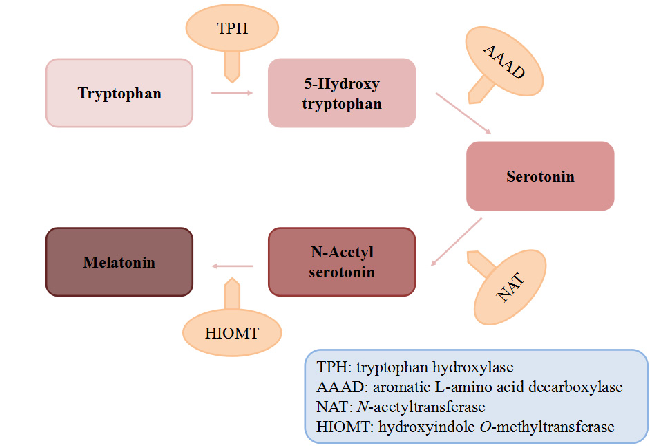

Biosynthetic pathway of melatonin from tryptophan is displayed, showing the sequential enzymatic steps through serotonin N-acetyltransferase and hydroxyindole-O-methyltransferase.

Dietary Sources and Bioactivities of Melatonin.